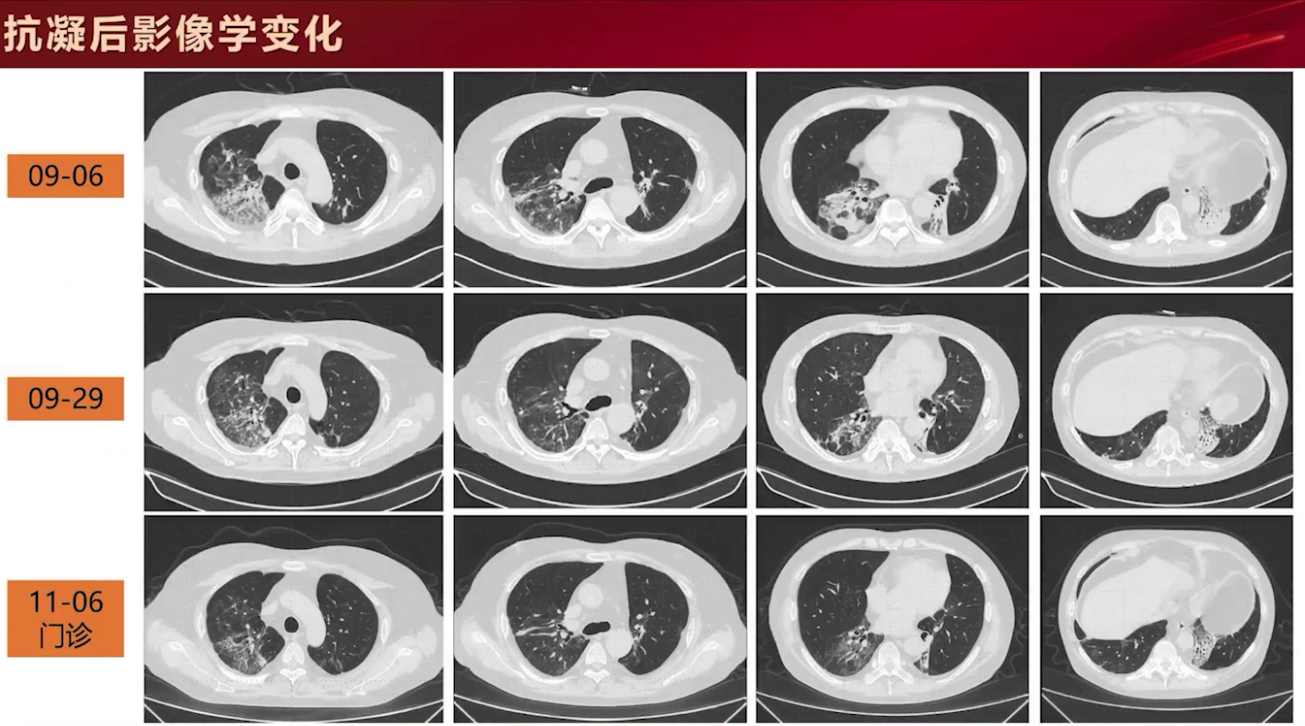

治疗上停用抗生素,恢复原糖皮质激素联合免疫抑制剂抗排斥治疗,加用利伐沙班15mg Q12h口服抗凝治疗,并对肺栓塞严重程度及病因进行筛查,结果显示心肌酶基本正常,四肢超声未见深静脉血栓形成,睡眠呼吸监测仅有轻度睡眠呼吸暂停低通气综合征,拔除深静脉导管未见肉眼栓塞。抗凝及抗血小板治疗后,患者氧合指数无明显改善,但吸氧浓度需求逐渐下降,过度通气情况好转,主观症状逐步改善。

9月29日复查胸部CTPA,两肺病灶总体呈吸收状态,但左下叶未好转且体积进一步缩小。

患者一般情况改善,国庆前出院。11月6日门诊复诊,两肺病灶仍在吸收,但左下叶病变吸收不明显。该患者肺上病灶存在肺栓塞,同时合并肺梗死和肺不张。